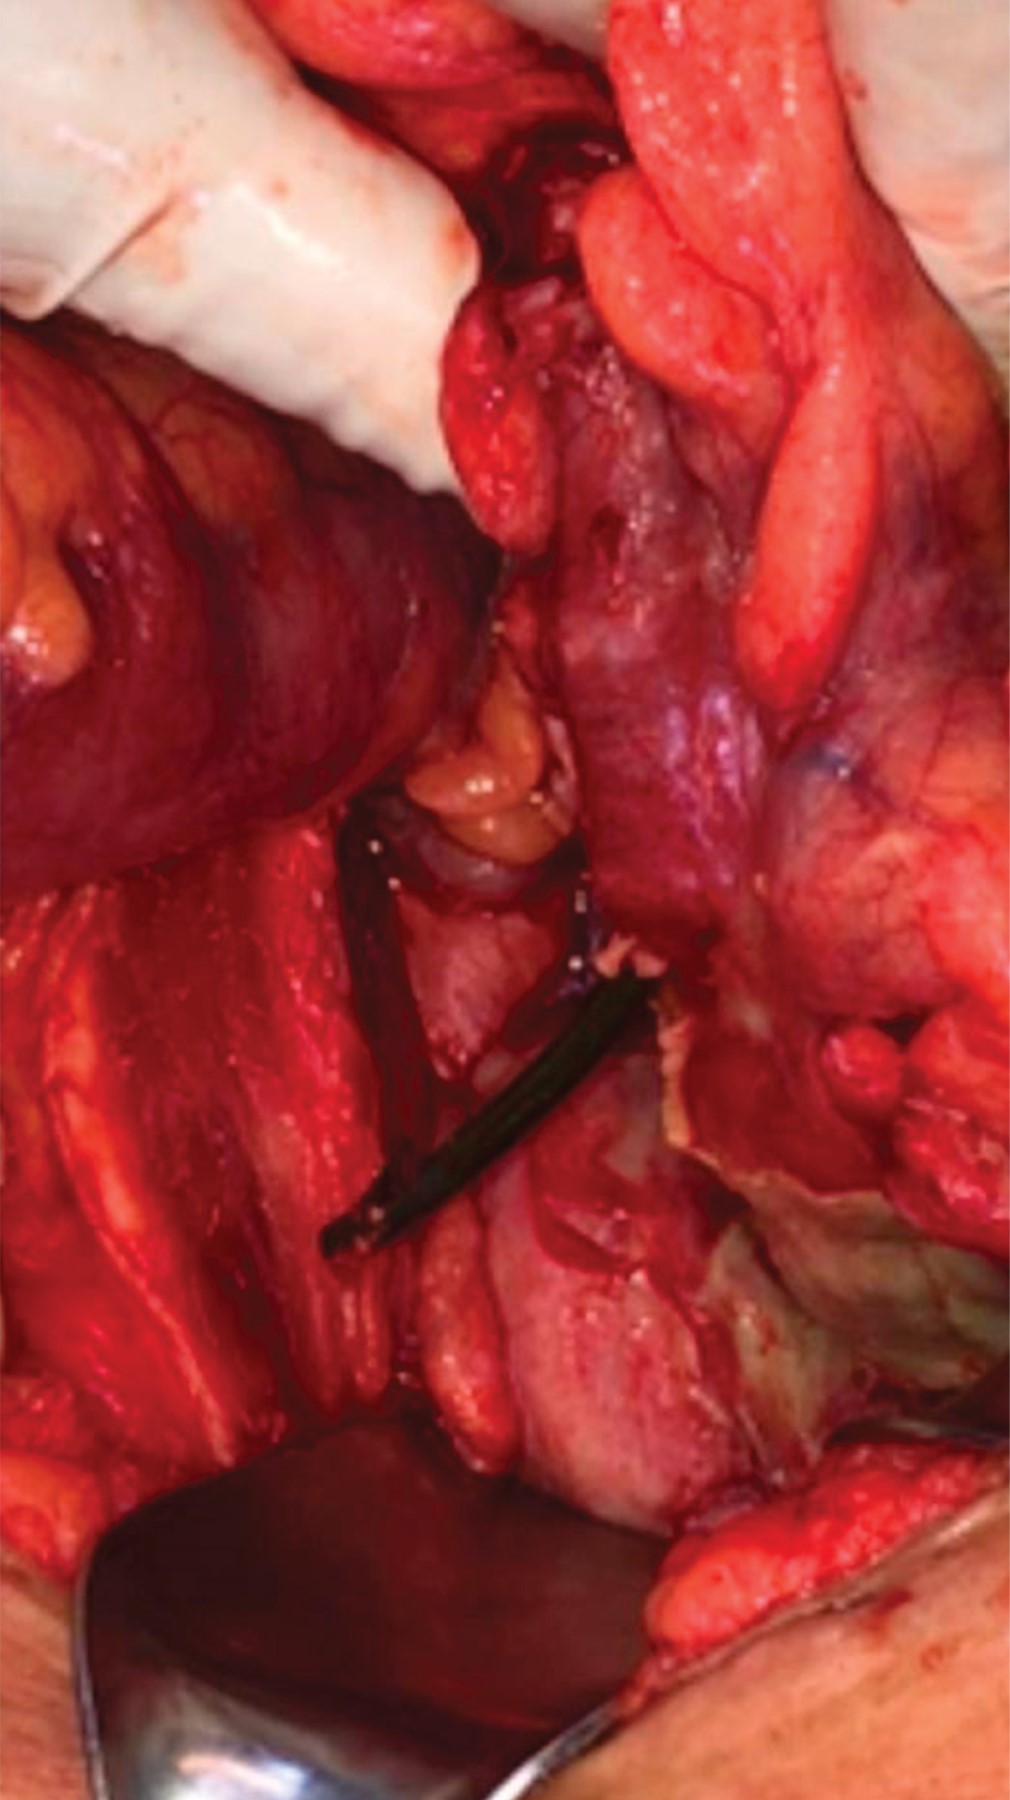

La paciente fue sometida a laparotomía exploradora, se encontró una perforación de un centímetro de diámetro a través de un divertículo del colon sigmoides secundario a la endoprótesis (Figura 3), y múltiples divertículos de sigmoides no complicados. Se extrajo la endoprótesis, se desbridaron los bordes intestinales de tejido sano y se realizó el cierre primario en dos planos, el interno por medio de sutura continua con poliglactina 910 calibre 3-0 y el externo a través de puntos tipo Lembert con seda calibre 3-0. No se evidenció peritonitis localizada o generalizada, pero de cualquier manera se colocó un drenaje de succión cerrada calibre 12 Fr, abocado a corredera parietocólica y pelvis. La evolución postoperatoria transcurrió sin incidentes, se administró ceftriaxona 2 mg cada 24 horas por vía intravenosa y metronidazol 500 mg cada ocho horas; la paciente egresó al cuarto día del postoperatorio, con indicación de cumplir cinco días más de metronidazol 500 mg cada ocho horas por vía oral.

Figura 3